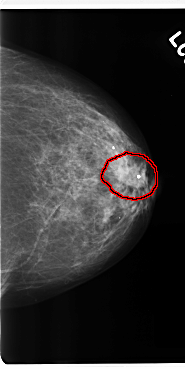

C_0206_1.LEFT_MLO

C_0206_1.LEFT_CC

FILE: C_0206_1.LEFT_CC.OVERLAY

TOTAL_ABNORMALITIES 1

ABNORMALITY 1

LESION_TYPE MASS SHAPE IRREGULAR MARGINS SPICULATED

ASSESSMENT 4

SUBTLETY 5

PATHOLOGY MALIGNANT

TOTAL_OUTLINES 1

BOUNDARY